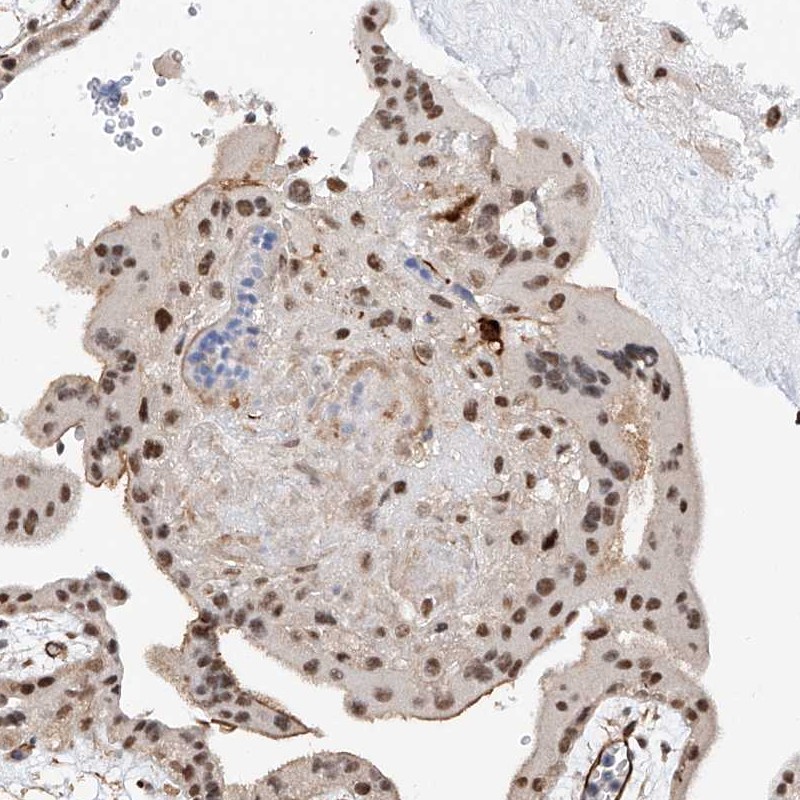

Immunohistochemical staining of human placenta shows distinct nuclear positivity in trophoblastic cells.